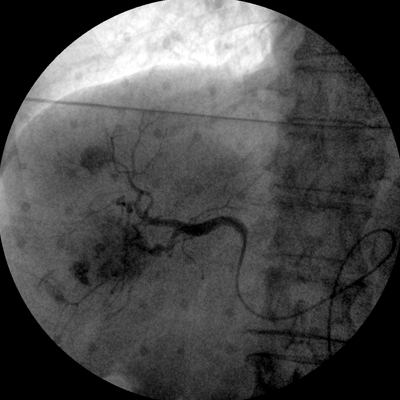

Clinical picture

临床图片